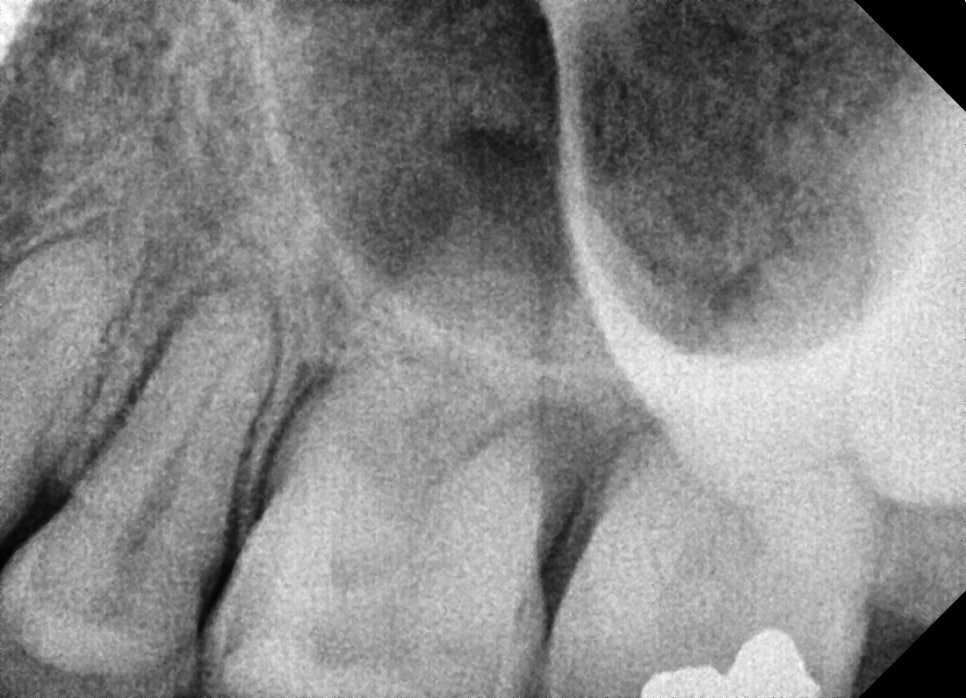

검사 결과 어금니 주변 잇몸 내부에 고름이 형성된

치주농양 상태였으며, 뿌리 주변 뼈가 손상된 상태가

확인되었습니다.

어금니 발치와 임플란트 식립

염증이 심한 어금니는 발치가 필요하였으며,

발치와 동시에 임플란트 식립이 진행되었습니다.

특히 어금니 부위는 뼈가 부족한 경우가

많기 때문에 뼈이식과 상악동 거상술이

함께 시행되었습니다.